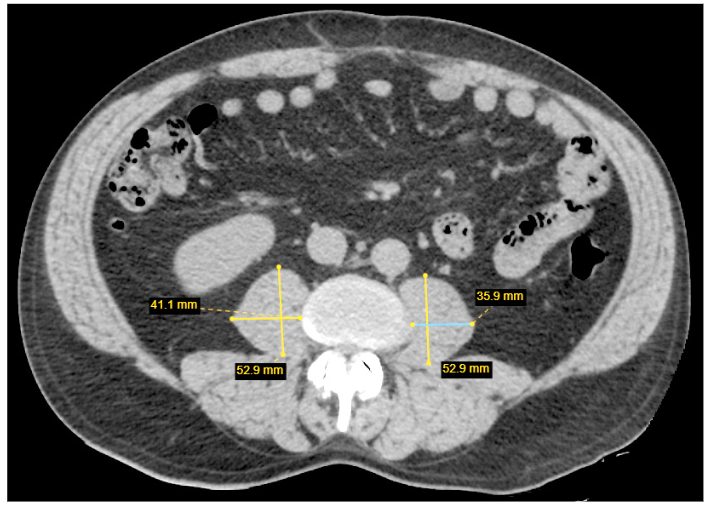

Patogiausias ir šiuo metu dažniausiai naudojamas tyrimas raumenų masei nustatyti yra KT. Ji gali būti laikoma „auksiniu standartu“ [26]. KT tyrimas gali tiksliai diferencijuoti raumeninį ir riebalinį audinį ir pateikti tikslią anatominę informaciją [26]. Šis dviejų audinių atskyrimas yra ypač reikšmingas vertinant riebalų depozitą raumenyse, žinomą kaip miosteatozė (angl. myosteatosis). Teoriškai, naudojant KT tyrimą, galima matuoti bet kurių kūno raumenų tūrį ir masę, tačiau šiandienos standartu laikoma Musculus psoas ploto matavimas L3 stuburo slankstelio lygmenyje [27] (2 pav.). Šio vieno raumens (o ne atskirų raumenų grupių ar bendro raumenų tūrio) matavimas yra patogus ir greitas būdas raumeniniam plotui vertinti, o mažas M. psoas raumens plotas yra patikimas neigiamas predikcinis veiksnys sergančiųjų onkologinėmis ligomis klinikinėms išeitims [27–29].

Minėtinas dar vienas KT tyrimo sarkopenijai vertinti privalumas – šis tyrimas yra neinvazinis. Be to, sergantiesiems skrandžio vėžiu viso kūno KT atliekamas rutiniškai nustatant ligos stadiją ir stebint pacientą dėl ligos recidyvo po operacijos. Minėto tyrimo taikymas būtų itin tinkamas pacientų, sergančių skrandžio vėžiu, sarkopenijai vertinti. Nereikėtų atlikti papildomo tyrimo, būtų galima tik papildomai įvertinti parametrus jau esančiuose vaizduose. Kalbamuoju atveju taptų nereikšmingi minimi KT trūkumai – kaina ar radiacinė apšvita, nes KT tyrimas jau yra standartinės klinikinės praktikos dalis.